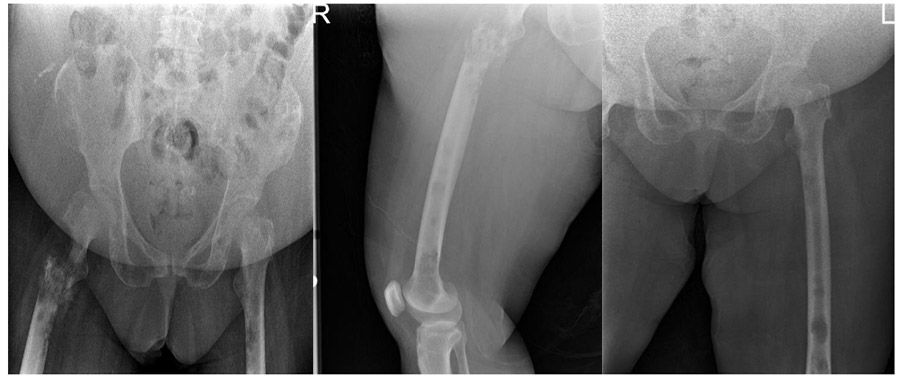

CASE 34: Risk of hip fracture and femoral fracture due to breast cancer metastasis.

Before the surgery: X-rays show widespread bone metastases in the pelvis and both femurs, and destruction and fracture of the upper end of the right femur.